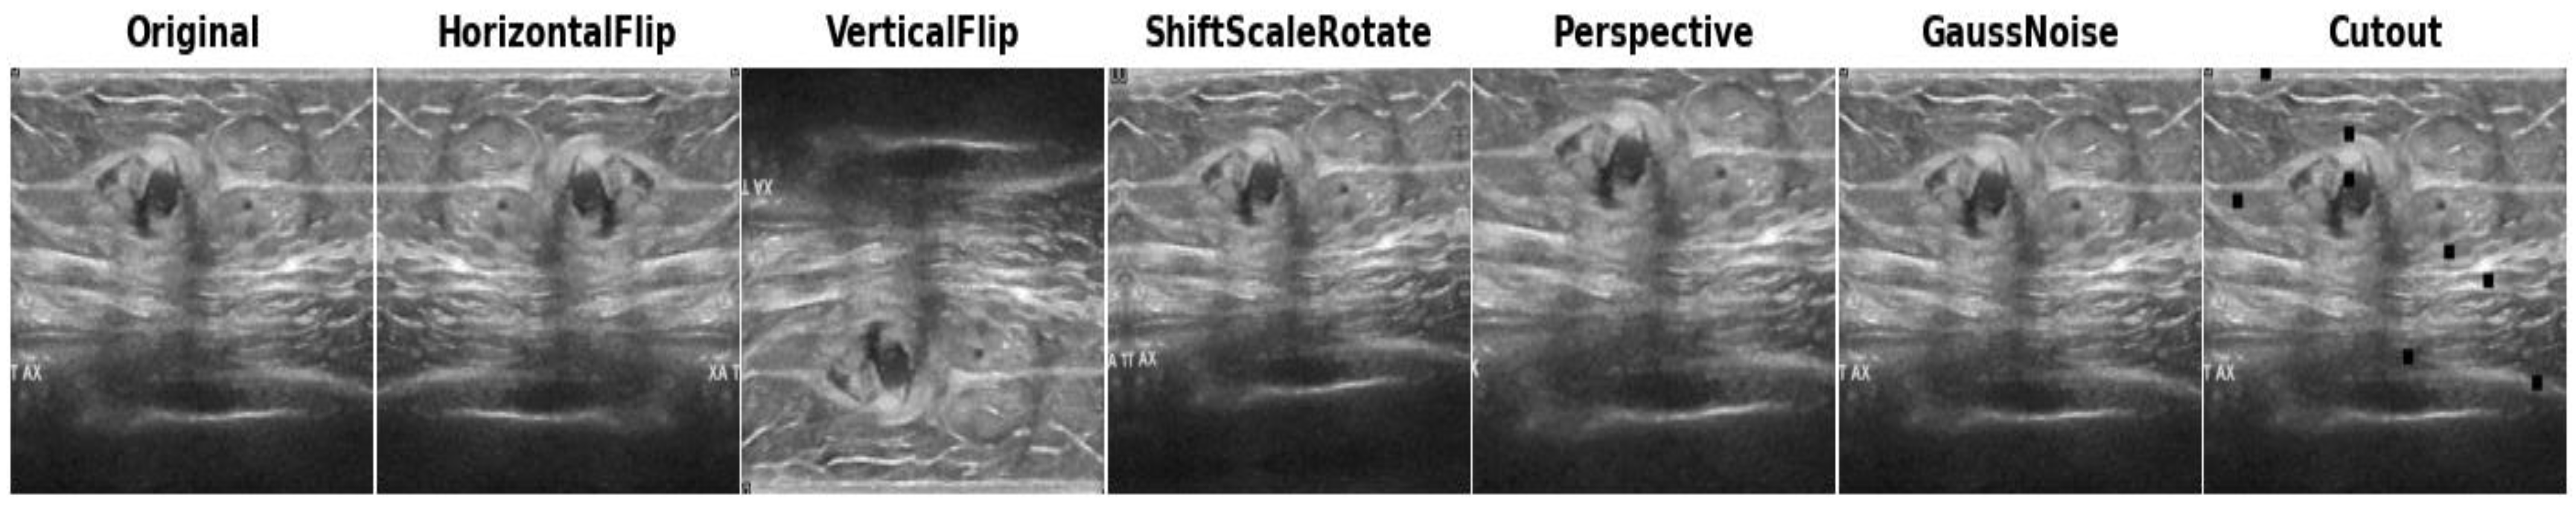

Before applying data augmentation, we partitioned the entire classification dataset into training and test datasets. The total dataset collected from all the sources comprised 3186 images for the classification of breast cancer in two categories: malignant and benign. Initially, the dataset was split into 80% (training data) and 20% (test data), resulting in 2548 images for training, with the remaining 638 images reserved for testing the models. Subsequently, we applied the following augmentation techniques exclusively to the training set (2548 images), while the test images were kept in reserve and not subjected to any processing techniques. Conventional augmentation such as horizontal flipping, vertical flipping, random shifts, scaling and rotations, perspective changes, and Gaussian noise addition have been applied to the real training images. These augmentation strategies were carefully selected to improve the model training and enhance the models’ ability to handle the diverse distortions often present in clinical settings. To provide a concise overview of the augmentation techniques employed, they have been organized in Table 1, while visual representations of the applied augmentation techniques can be found in Figure 3.